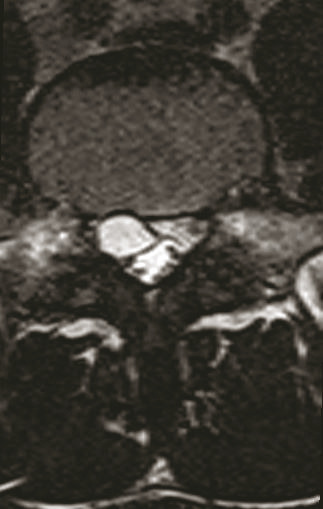

L’IRM du rachis lombaire obtenue une semaine plus tard retrouve une formation kystique développée en postéro-latéral droit du corps vertébral de L5 venant comprimer la racine L5 droite et affleurant la racine S1 droite à son émergence, évocatrice d’un kyste arthrosynovial extramédullaire et extradural (photos).